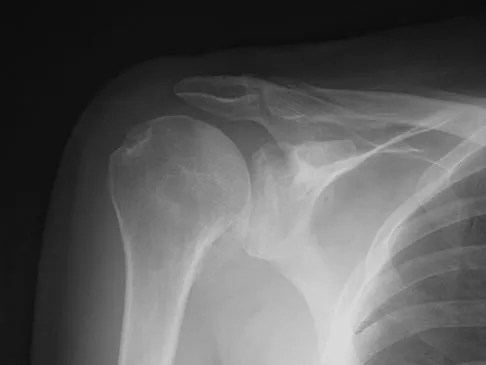

A 62-year-old man with a long history of right shoulder pain and weakness is scheduled to undergo hemiarthroplasty. Based on the radiographs shown in Figures 6a through 6c, what preoperative factor will most affect postoperative functional outcome?

The radiographs reveal osteoarthritis and proximal humeral head migration. Integrity of the rotator cuff must be questioned based on these radiographic changes. The status of the rotator cuff is the most influential factor affecting postoperative function in shoulder hemiarthroplasty. The coracoacromial ligament provides a barrier to humeral head proximal migration in the face of a rotator cuff tear. The radiographs do not indicate significant humeral head or glenoid erosion. Acromioclavicular arthritis is often asymptomatic. Iannotti JP, Norris TR: Influence of preoperative factors on outcome of shoulder arthroplasty for glenohumeral osteoarthritis. J Bone Joint Surg Am 2003;85:251-258.